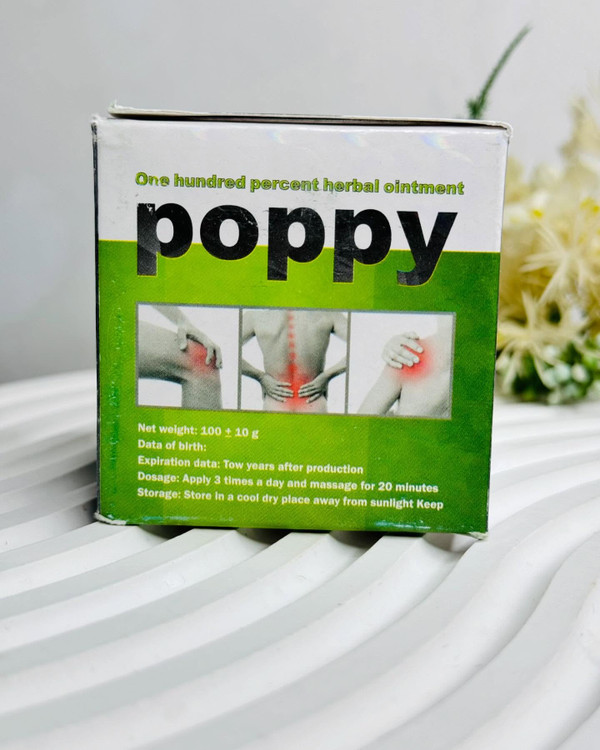

دیگه با پماد ضد درد گیاهی هیچ درد عضلانی رو حس نمیکنی تسکین و درمان انواع دردهای موضعی گرفتگی رگها و عضلات ضرب دیدگی استخوان کمر درد پا درد درد سیاتیک دردهای عضلانی دست و پا درد ضرب دیدگی استخوان تسکین دهنده درد گرفتگی عضلات خشکی از خواص پماد خشخاش : بهبود دهنده کمر درد بهبود دهنده سیاتیک بهبود دهنده دست و پا درد بهبود دهنده کتف درد بهبود دهنده زانو درد بهبود دهنده گردن درد بهبود دهنده گرفتگی عضلات بهبود دهنده خشکی عضلات بهبود دهنده دردهای عضلانی ============================= روش مصرف : روزی به به مدت 10 دقیقه با کمی پماد خشخاش محل درد را به خوبی ماساژ دهید سپس روی آن یک پلاستیک بگذارید و با یک پارچه تمیز ببندید تا پماد فرصت جذب و نفوذ به بافت ها و مفاصل را داشته باشد.